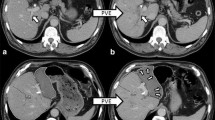

The ICG-R15 value, however, reflects the function of the TFLV but not that of the FLR, and whether or not a gain of FLR volume as a result of PVE is a true reflection of an improved FLR function remains unclear. Several studies have suggested that the FLR function increases before hypertrophy of volume is apparent on CT [49, 50]. Uesaka et al. measured the biliary ICG concentration from multiple biliary drainage tubes placed for draining the entire liver in 8 patients who underwent right PVE and reported that the ratio of ICG excretion in the FLR to ICG excretion in the whole liver increased 20% on average after PVE, while the FLR/TFLV ratio increased only 8% on average [49].

Pattern of FLR volume regeneration

A number of studies have evaluated the relationship between volume regeneration of the FLR and functional recovery of the FLR. Studies evaluating chronological changes in the remnant liver volume after donor hepatectomy for living donor liver transplant showed a rapid volume increase in the early (within 3 months) postoperative period despite functional recovery taking up to one year for normalization [51, 52]. Maeda et al. recently evaluated the volume change following PVE and also 7 days after extended hepatectomy in 289 patients with perihilar cholangiocarcinoma [53]. They showed a significant negative correlation between the kinetic growth rate (kGR), defined as the change in the FLR/SLV ratio [%] divided by the interval [weeks] [54] after PVE and kGR after hepatectomy. This result makes sense from the viewpoint that remarkable FLR hypertrophy occurred before rather than after surgery and was associated with a reduced incidence of PHLF. These authors also showed that there was no association between the kGR after either PVE or hepatectomy and the incidence of hepatic insufficiency. They concluded that there was a discrepancy between the recovery of the FLR volume and the recovery of the FLR function in the early phase of liver regeneration [53]. Because most patients in their series had hilar cholangiocarcinoma, other factors, such as perioperative cholangitis, might have affected the incidence of PHLF.

Two methods are based on CT. Nagino et al. evaluated the change in the FLR volume and plasma disappearance rate of ICG (kICG) in patients who underwent extended hepatectomy following PVE for biliary cancer; the study included 176 survivors and 17 patients who died due to postoperative complications. The authors showed that FLR hypertrophy did not distinguish between survivors and non-survivors, but the kICG after PVE did, so they proposed a kICG of the FLR ≥ 0.05, with the kICG of the FLR defined by the formula kICG × FLR [ml]/TLV [ml], as a criterion for safe hepatectomy [57]. This cut-off value was validated in their later series [58, 59]. Shindoh et al. proposed evaluating the FLR function using the kGR, defined as the increase in the FLR volume from baseline divided by the length of time in weeks after PVE, and this was shown to be a better predictor of postoperative morbidity and mortality than the preoperative FLR/SLV ratio or FLR hypertrophy rate in a large series of patients [54]. However, in another series, kGR did not correlate with outcomes after ALPPS [60]. In fact, the high incidence of morbidity and mortality suggested that no volumetric measurement predicted outcomes after ALPPS.